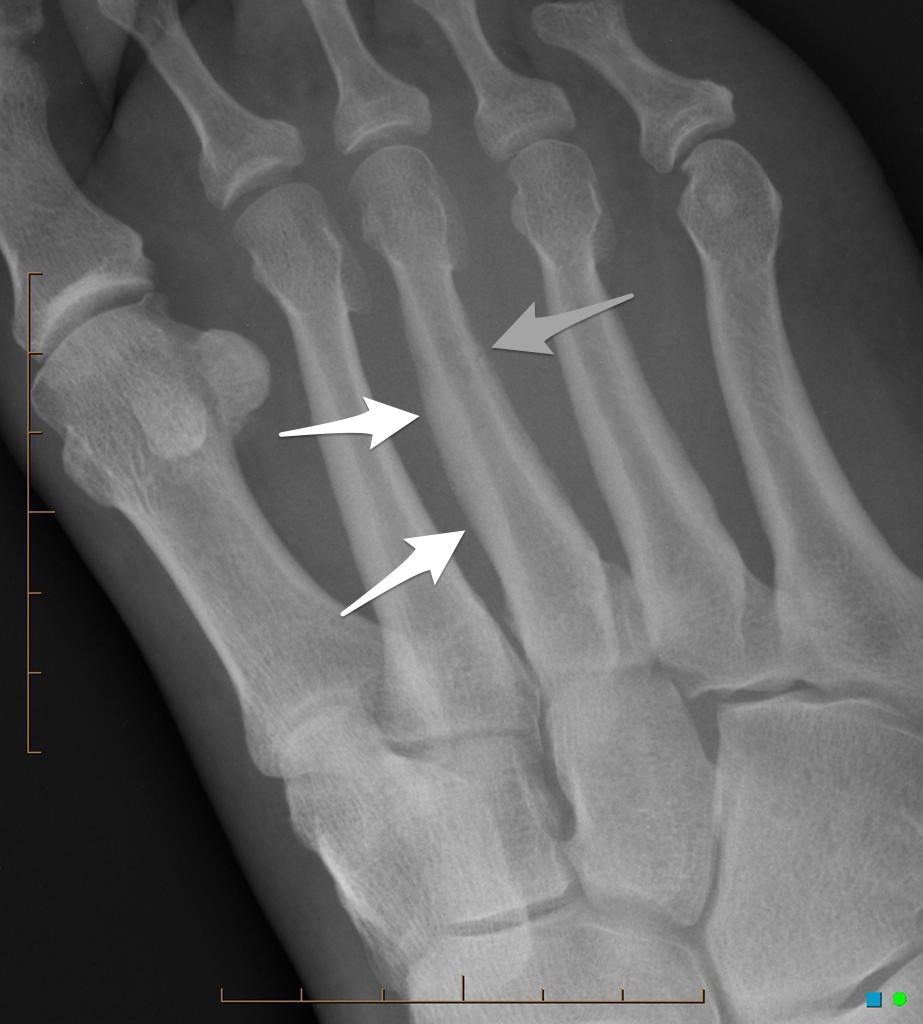

Gãy xương mệt mỏi

» Thông tin: Nữ giới – 23 tuổi.

» Lâm sàng: Đau bàn chân.

# Gãy xương bàn II

# Gãy xương bàn III

# Gãy xương mệt mỏi xương bàn V bàn chân.